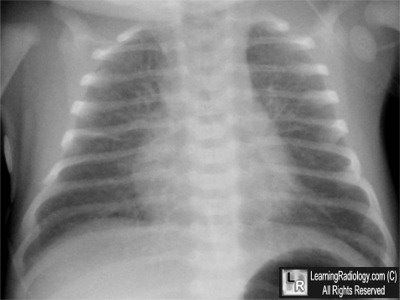

Frontal view of chest at birth

What is the most likely diagnosis?

- Term infant at birth with mild respiratory distress

4. Transient Tachypnea of the Newborn

Transient Tachypnea of the Newborn

- Usually full-term or slightly pre-term

- Some delivered by C-section; some precipitous labor

- Mild respiratory distress immediately after birth

- Improve within several hours